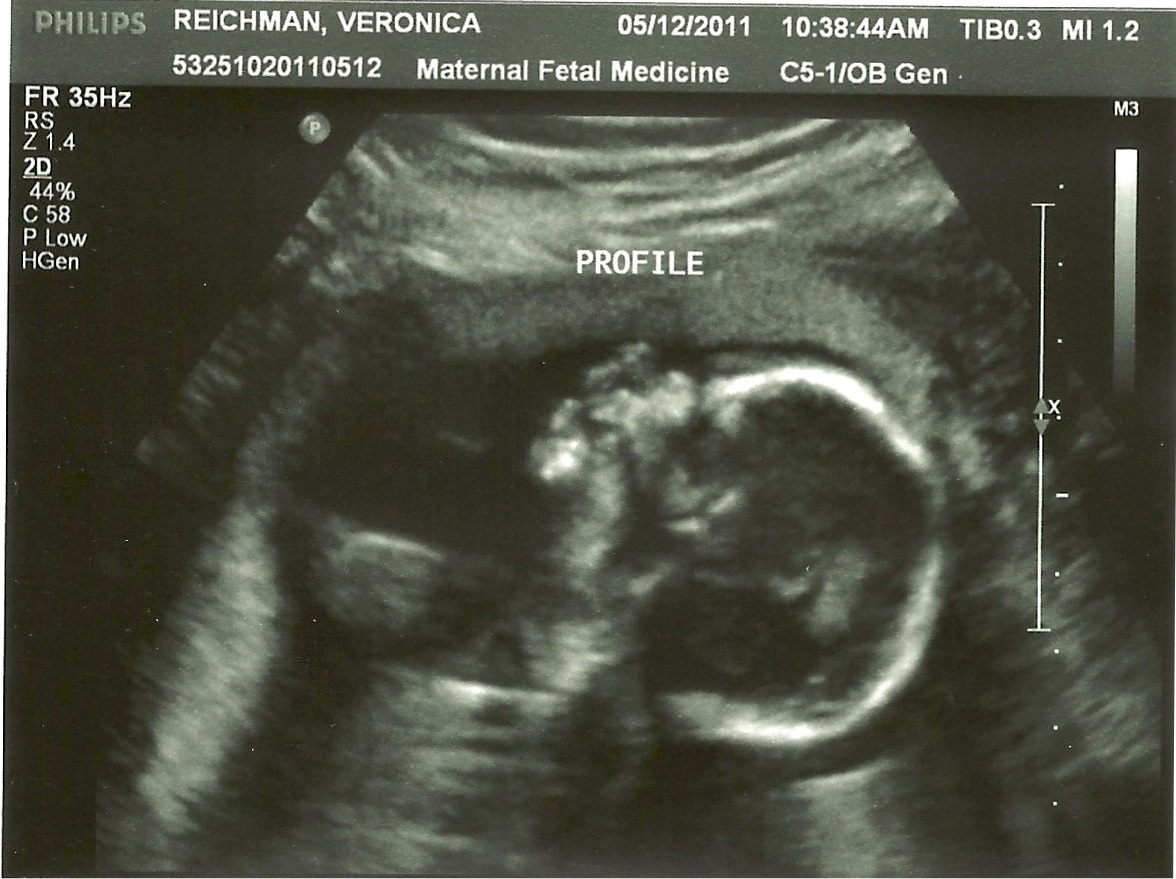

That’s right! Mike and Veronica are expecting a boy in October. They invited me to go along for the ultrasound and “meet” my newest grandson! We saw his hands, fingers, feet, legs, head, spine… and his precious beating heart… all being wonderfully knit together by God into a perfect little boy… what a miracle!